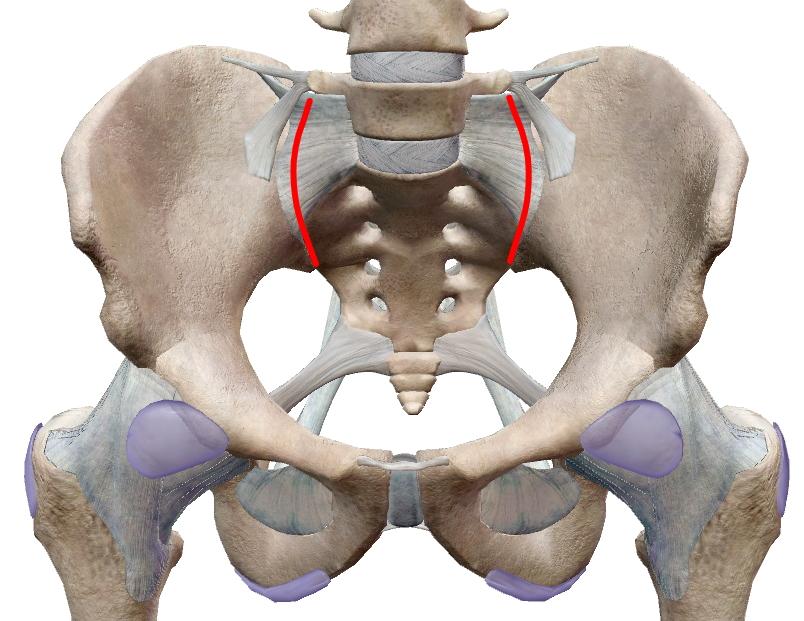

線維性軟骨結合は、幼児期の寛骨(腸骨・恥骨・坐骨)、恥骨結合。

ちなみに仙骨と腸骨からなる仙腸関節は未だに定義が定まっていませんが、部分的な滑膜関節と部分的な線維性軟骨結合の両方を持ち合わせている説が現在濃厚。関節腔は非常に小さく動きは極小さいという点は今までと同じです。

凸凹ザラザラな耳状面で接するのに骨化しない点が謎な仙腸関節。他の関節についても曖昧なところはいくらかあります。

| 平面に近い関節面が滑るように動く多軸関節。関節面が小さいので可動範囲は極めて小さい。 椎間関節、仙腸関節、肩鎖関節、脛腓関節、手根間関節、足根間関節、豆状骨関節。 *仙腸関節、脛腓関節は、関節面の半分が線維性軟骨結合が占め関節腔が非常に小さいので『半関節』とも。 |